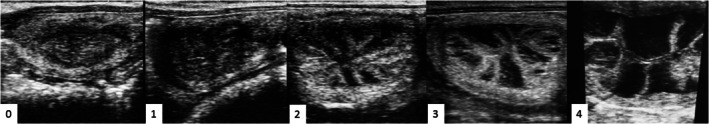

A longer endometrial exposure to estradiol before progesterone has been shown to be beneficial in cyclic and acyclic recipient mares. Therefore, the selection of an estradiol ester that promotes longer endometrial exposure to estradiol using a single administration would be advantageous when preparing acyclic mares as embryo recipients. This study investigated plasma estradiol profiles in acyclic mares after a single administration of 17-β estradiol (17-β), estradiol benzoate (EB) and estradiol cypionate (EC), and the correlation between plasma concentrations and endometrial edema. Fifteen non-cyclic mares were divided into groups 17-β (n = 5), EB (n = 5) or EC (n = 5), receiving a single dose of 10 mg of the respective hormone. Blood sample collections and transrectal ultrasonography were performed every 6 h from hour 0 to 12, every 12 h from 12 to 48 h, and every 24 h from 48 to 120 h after hormone administration. Five of the acyclic mares were used during the breeding season as a cyclic control. Greater median concentrations were detected using EB (38.6 pg/mL; p < 0.05). For 17-β, peak concentration was observed at 6 h (29.7 pg/mL) and decreased 24 h after administration (5.9 pg/mL; p < 0.05). In the EC group, there was a modest peak starting from 12 h (11.7 pg/mL; p < 0.05), remaining relatively constant until 120 h. A more rapid increase of edema to moderate and high scores was found when using 17β estradiol, although edema scores and persistence until Day 5 were similar among the oestrogens used. A correlation between estradiol concentration and endometrial edema was only seen when using EC, and this hormone also produced the most similar concentration values to those found in natural cycling mares. Therefore, it is likely that EC would be a suitable hormone for preparing acyclic mares as embryo recipients.